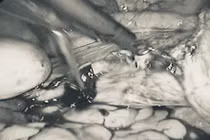

Ca phẫu thuật nội soi cắt tử cung, bảo tồn hai phần phụ được thực hiện bởi ThS.BS Phạm Trọng Thuật, cùng các bác sĩ Khoa Phụ sản, Bệnh viện Đa khoa Phương Bắc. Ca mổ diễn ra thuận lợi, an toàn. Sau phẫu thuật, mẫu bệnh phẩm đã được gửi làm giải phẫu bệnh để đánh giá mô bệnh học.

cat-tu-cung1.jpg

Ảnh BVCC